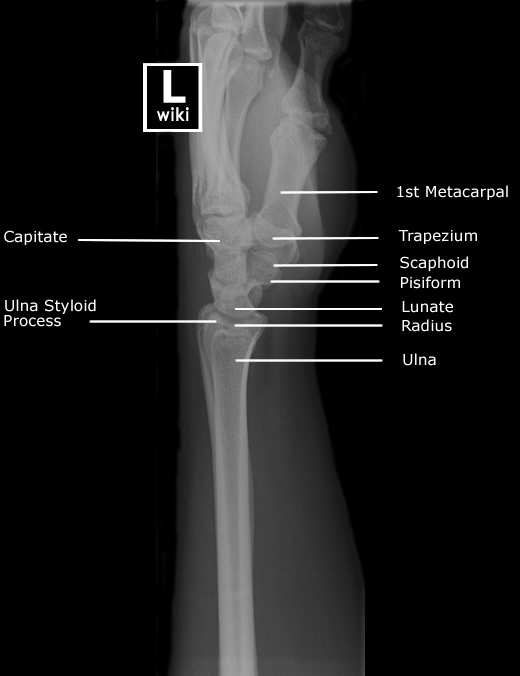

| [Anatomy] Wrist(손목) (0) | 2024.01.15 |